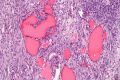

卵巢甲状腺瘤英文名:struma ovarii),是一类中胚层畸胎瘤英语-{monodermal teratoma}-的罕见病变,它包括很多甲状腺组织,并可能引起甲状腺功能亢进症[1]。卵巢甲状腺瘤的病发并不仅限于卵巢部位。绝大多数的卵巢甲状腺瘤是良性肿瘤;但是研究也发现一些恶性肿瘤的病例[2]

尽管未能对该型肿瘤做出精确的诊断,超声波仍然能够发现异化的大型甲状腺瘤。超声波能够发现一个混合囊性或实性,并能够确定肿瘤的病理学成像核磁共振成像可以探测出更多细节:囊性部位呈现出高密度或低密度成像,可能是因为肿瘤中的凝胶状胶体。在病理学上,没有发现脂肪组织[3]